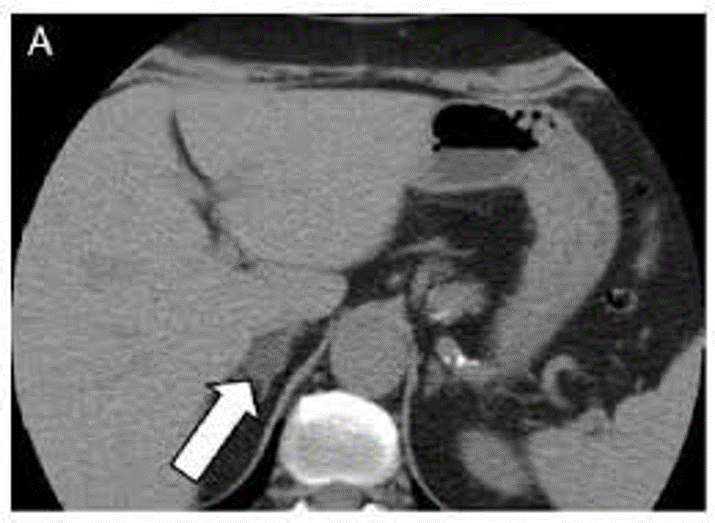

Case Report: 80 year old woman came to the internal medicine ambulatory for bad hypertension (HY) control: two recent accesses in first aid (FA) for hypertensive crisis with values of 205/100 mmHg resolved with clonidine and furosemide. History of ischemic heart disease, diabetes mellitus, dyslipidemia, and HY from 6 years treated with ramipril and amlodipine with good control. Routine exams were normal. We dimetted patient increasing ramipril and adding calcium antagonist. Ten days later she came back to FA for a new episode of severe hypertension (180/100 mmHg). We found: hypokalemia (2.8 mmol/l) and no good glucose control (Hbglicata 8.9%). We decided to suspend ramipril and added clonidine (TTS2) and amlodipine. Urinary electrolytes 24 hours, aldosterone and renin in plasma: normal Kaliuria, high aldosteronemia both in clino and ortho statism, reninemia normal and relationship aldosterone/renin was high. She underwent abdomen functional magnetic resonance magnetic confirmed adrenal 28mm nodule in the posterior region of the right adrenal gland. She began therapy canrenone100 mg and clonitinaTTS2. She had a good response.